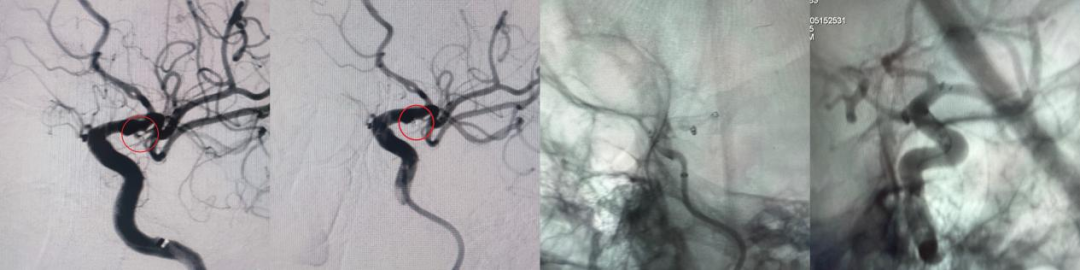

49岁女性,近期23点半因突发头痛伴恶心2小时就诊,CT提示蛛网膜下腔出血。神经外科会诊后明确诊断:前交通动脉瘤破裂(此次责任动脉瘤)及左侧颈内动脉眼动脉段未破裂动脉瘤。黄宪团队综合评估后,决定连夜实施急诊手术先处理破裂动脉瘤,待病情稳定后再处理未破裂病灶。手术连夜顺利完成,患者术后恢复良好,一个月后状态稳定,再次入院接受血流导向装置置入术处理另一动脉瘤。分期治疗策略有效降低了单次手术创伤与风险,这种“先救急、再治缓”的策略,缩短了手术时间、降低了术中血管痉挛、血栓形成等并发症风险,同时避免了急性期口服抗血小板药物治疗带来的潜在风险。

图2:前交通动脉瘤弹簧圈栓塞术前后造影